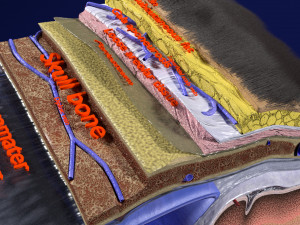

A blend model of brain along with its covering layers (meninges), skull bone and scalp labelled in detail and anatomically precise. The parts depicted are white, gray, pia, arachnoid, dura, bone, skin, fat, aponeurosis, periosteum, falx cerebri and more.

The material is high resolution image textures and normal maps based on non overlapping UVs. The texture and normal maps are packed with the blend file itself.